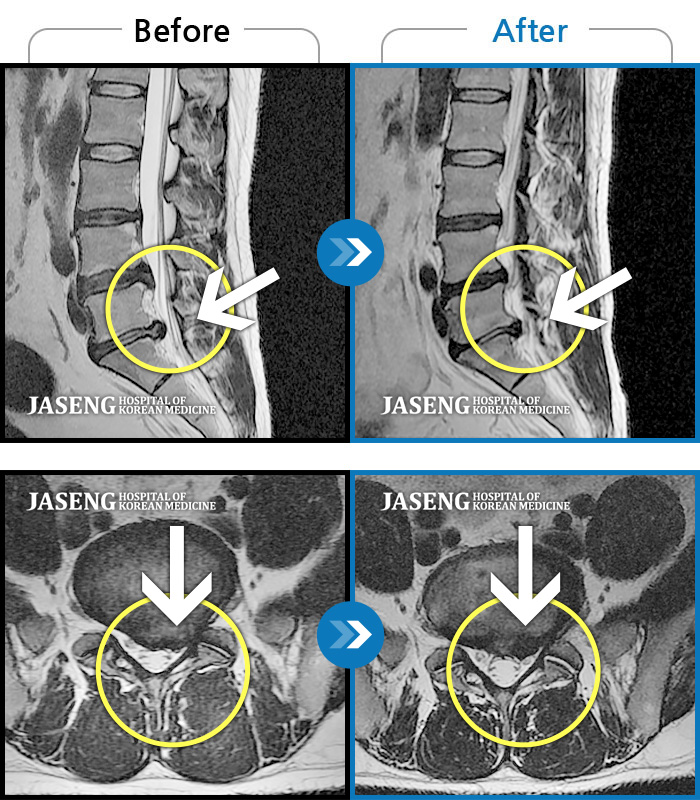

MRI 치료사례

허리디스크

일산 · 김태용 원장

허리 골반통증이 극심했다.

촬영시기

2021.02.06 ~ 0222.01.15

허리와 좌측 하지 방사통이 심하시어 보행이 거의 힘들었다.

2021.03.06 ~ 2021.07.15